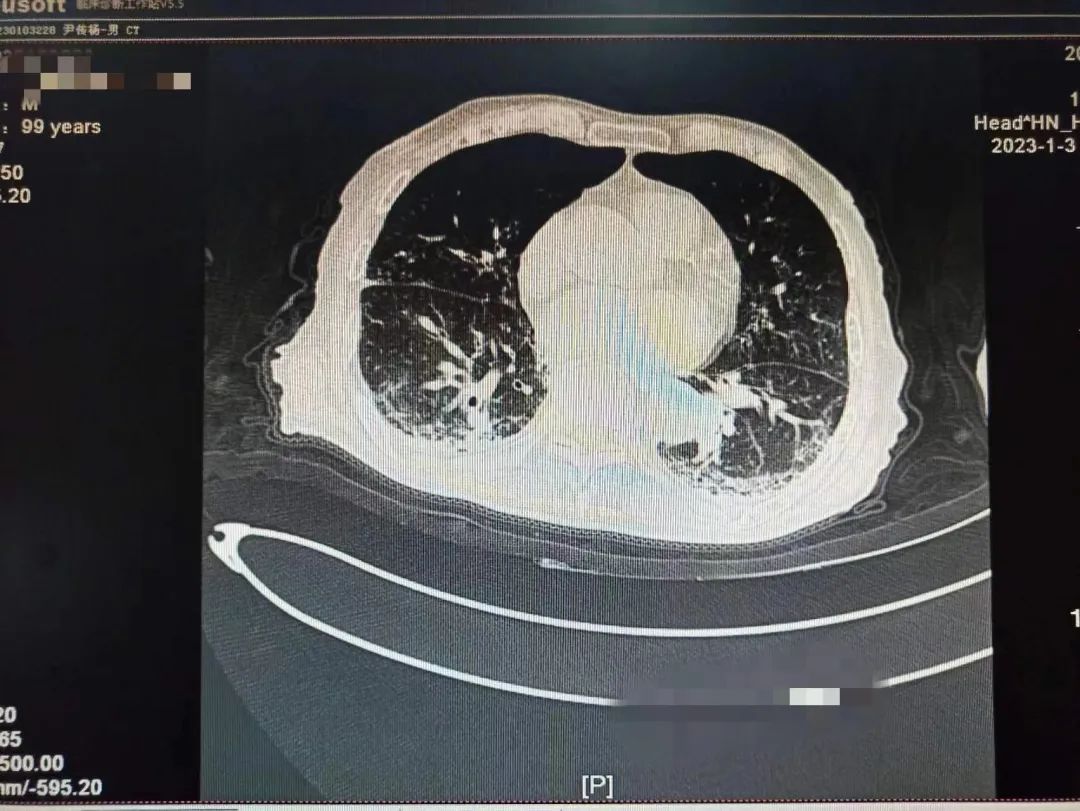

学校一附院呼吸与危重症医学科一名患者刘老爷子还差几天就到100岁生日,该患者从2022年12月22日开始持续发热,咳嗽。一开始只是以为普通的感冒,没特殊注意,后逐渐出现胸闷,乏力,精神差,在当地医院完善肺部CT,两肺大片病毒性肺炎表现,新冠核酸阳性,家属急送一附院就诊。

不放弃每一个生命!全力救治!经过连续数日医护团队的精心救治,2023年1月9日,呼吸与危重症医学科医护团队再次对老人病情进行综合评估,检查显示患者肺部病灶明显吸收,精神明显好转,可以正常活动,和感染前身体体征一致。出院当天老人握着刘家昌主任的手激动的说:“多亏刘主任了,要不是你和咱们医院医护团队,我这关是闯不过去了,我还以为我过不去这一百岁坎了。”刘家昌主任对老人和家属详细交代了出院康复指导意见及注意事项。